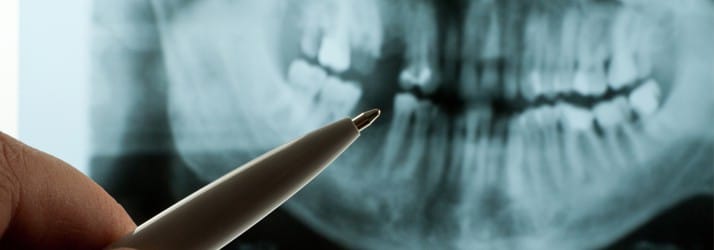

3-D Cone Beam X-ray Unit

Traditional dental x-rays are 2-dimensional. While they are useful in diagnosing common dental issues such as tooth decay or periodontal disease, they are limited in terms of detail and accuracy. Our cone beam unit can capture a high-definition 3-D representation of your teeth, jawbone, and surrounding structures such as the mandibular nerves and the maxillary sinuses. The final x-ray is obtained through a series of radiographic pictures that are stitched together, resulting in an anatomically-accurate image.

The final diagnostic image can be manipulated and viewed from any perspective, which allows Dr. Arooni to plan treatments with unmatched precision. This is particularly useful in dental implant placement. Because the cone beam unit can provide exact measurements, the height and width of the bone can be assessed to determine what size implant will be the most beneficial. Additionally, by evaluating the jawbone density, Dr. Arooni can determine which location will yield the most successful long-term results.

Conventional 2-D dental x-rays often take several minutes to complete. Our 3-D cone beam unit can perform an entire scan in less than one minute. It also emits 90 percent less radiation than traditional x-ray machines, making it a safer and more efficient option for our patients.